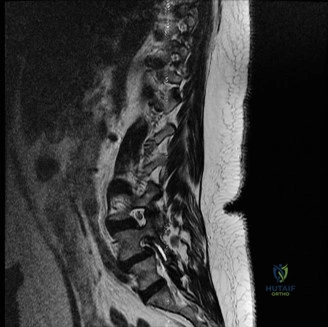

To contextualize the decision-making algorithm, consider the classic presentation of a middle-aged patient with multiple medical comorbidities. A paradigmatic case involves a 48-year-old obese female (Body Mass Index of 43) with poorly controlled diabetes mellitus who presents with severe, unrelenting low back pain, fevers, and chills. Advanced imaging, specifically magnetic resonance imaging (MRI), typically demonstrates discitis involving the L4–5 disc space with adjacent osteomyelitis of the L4 and L5 vertebral bodies. Crucially, in many early or medically responsive cases, there is an absence of epidural abscess formation, and standing radiographs reveal relatively normal sagittal and coronal alignment. When such a patient is neurologically intact—lacking saddle anesthesia, bowel/bladder incontinence, or upper motor neuron signs—the immediate clinical imperative shifts from urgent surgical decompression to aggressive pathogen identification and targeted antimicrobial therapy.

Pre-Operative Planning, Templating, and Patient Positioning

When surgical intervention becomes unavoidable, meticulous pre-operative planning is the cornerstone of a successful outcome. Advanced imaging is non-negotiable. An MRI with and without gadolinium contrast is the gold standard for defining the extent of the epidural abscess, the degree of neural compression, and the involvement of adjacent paraspinal musculature (e.g., psoas abscess). T1-weighted images typically show hypointense signals in the infected marrow, while T2-weighted and STIR sequences reveal hyperintense fluid and edema in the disc space and vertebral bodies. Gadolinium enhancement highlights the vascularized inflammatory phlegmon and the capsule of any abscesses.

In addition to MRI, a fine-cut computed tomography (CT) scan is essential for evaluating bony destruction. CT allows the surgeon to assess bone stock for pedicle screw purchase and to template the size of the interbody cages required for anterior column reconstruction. Upright standing radiographs (if the patient can tolerate them) or full-length supine films are necessary to evaluate global spinal alignment and regional kyphosis.